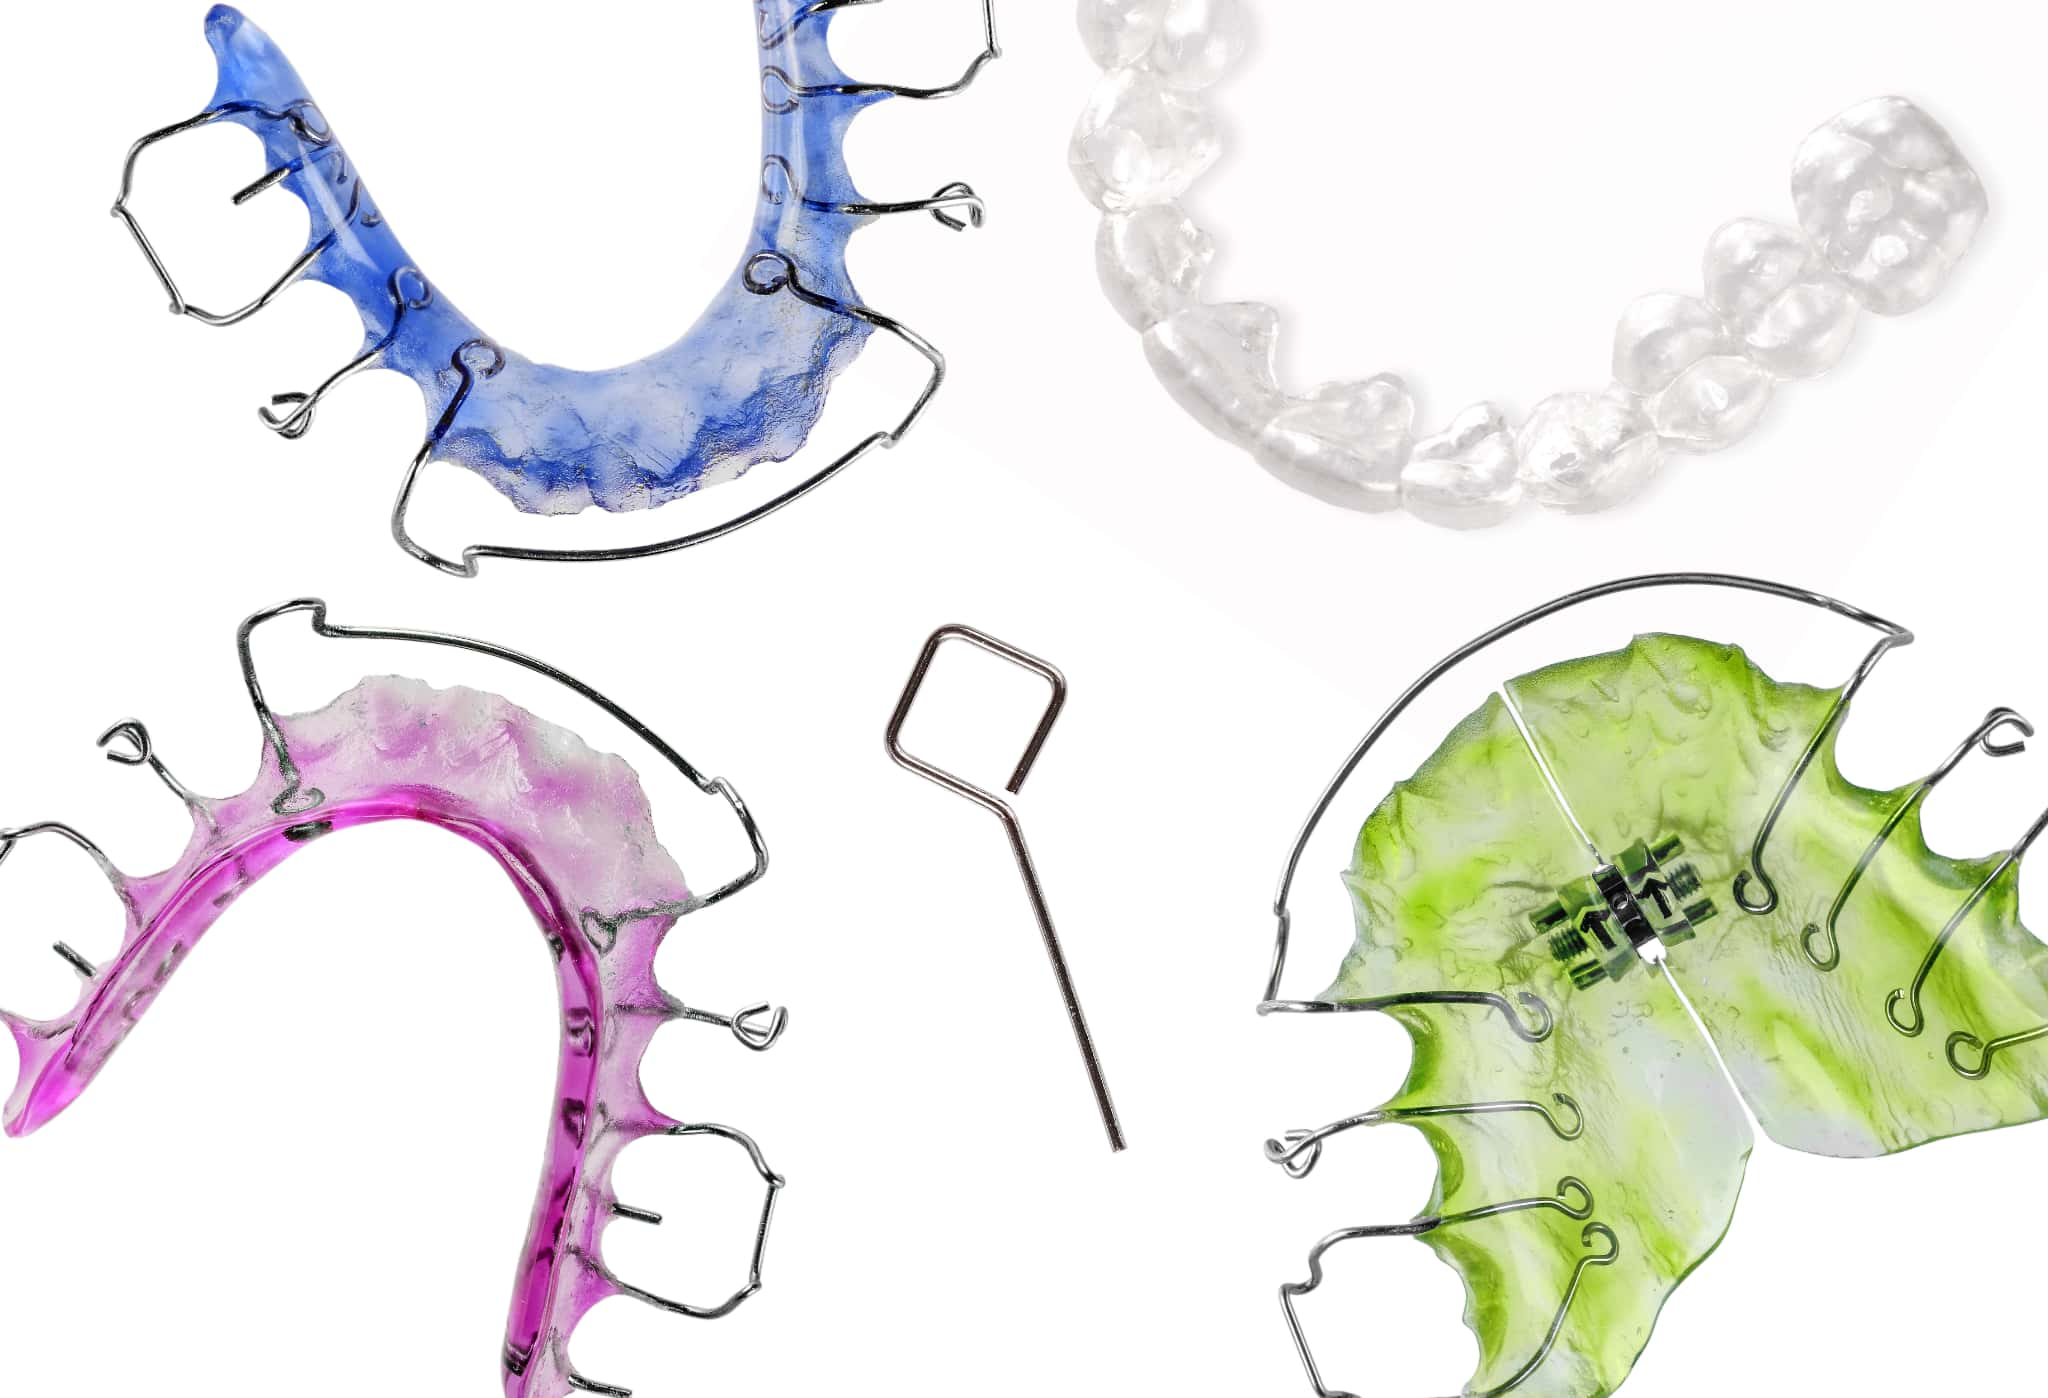

マイオブレース

マイオブレースは、受け口の原因とされる口呼吸や舌の位置、飲み込み方、姿勢などの悪い癖を改善することで、自然な成長を促す治療法です。装置は取り外し式で、主に自宅での装着とトレーニングを組み合わせて進めていきます。

成長期に行うことで、顎の発育と筋機能を整え、将来的な歯列不正や噛み合わせの悪化を予防できます。

インビザライン・ファースト

インビザライン・ファーストは、マウスピース型の矯正装置を使って受け口を治療する方法です。成長期の子どもの顎の発達を利用しながら、歯並びと噛み合わせの両方を整える治療法として注目されています。この方法では、透明なマウスピースを1日20時間以上装着し、1〜2週間ごとに交換しながら歯の位置を少しずつ動かしていきます。

また、食事や歯磨きの際には簡単に取り外しができ、矯正装置に不快感を覚えることも少ないため、ストレスが少ないのも大きな特徴です。

床矯正

床矯正(しょうきょうせい)は、取り外し可能な装置を使って顎の幅を広げる矯正方法です。装置は主に夜寝ている間や家にいるときに装着し、歯がきれいに並ぶためのスペースを確保します。受け口においては、上顎の成長を促して下顎とのバランスを整える効果が期待できます。

ただし、治療の効果を十分に得るためには、指示された時間しっかりと装着する必要があります。そのため、お子さま自身が治療の目的を理解するとともに、保護者の方が声かけや見守りを続けることも大切です。

急速拡大装置

急速拡大装置は、上顎の幅を広げるための特殊な装置です。上顎が狭いことで下顎が突出して見えている場合、この装置によって骨格のバランスを整えます。治療は数か月から半年ほどで、拡大後は上顎にスペースができ受け口が改善されやすくなります。

プレオルソ

プレオルソは、就寝時に装着するやわらかいマウスピース型の矯正装置です。舌の位置や口呼吸、唇の使い方など、子どもに多く見られる悪習癖を改善しながら、歯並びや噛み合わせのバランスを整えることを目的としています。

プレオルソは取り外しが可能なため、日中は自由に過ごせるという利点があります。また、柔らかい素材で作られているため、装着時の不快感や痛みが少なく、子どもにとっても続けやすい治療法といえるでしょう。

受け口の根本原因である舌や口周りの筋肉の使い方を整えることは、矯正後の後戻りを防ぐうえでも重要です。プレオルソは、そうした口腔機能の発育をサポートしながら自然な歯並びへと導いてくれる装置として注目されています。